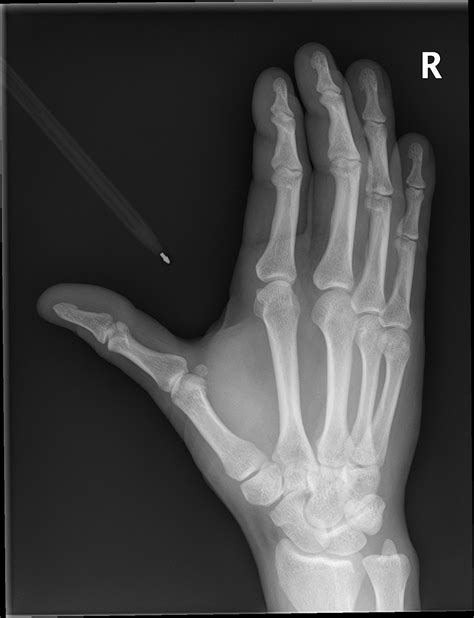

When you visit a medical imaging department after a sudden injury or persistent discomfort, the first step in diagnosing your hand is almost always a diagnostic imaging scan. Seeing an X Ray Normal Hand is often the baseline that radiologists use to compare against potential fractures, dislocations, or soft tissue irregularities. Understanding what a healthy hand looks like on a radiograph can help patients feel more at ease and better understand the information their healthcare provider is sharing. Whether you are dealing with a minor sprain or just curious about anatomy, the standard radiographic projection of the hand provides a wealth of information about the structural integrity of your bones and joints.

The human hand is a marvel of biological engineering, consisting of 27 individual bones. When a technician captures an X Ray Normal Hand, they are looking for specific structures that demonstrate proper alignment and density. The hand is broadly divided into three main sections, all of which are clearly visible on a standard radiographic projection:

• Carpals: The eight small, irregular bones that make up the wrist (carpus). These act as a bridge between the forearm bones and the hand.

• Metacarpals: The five bones that extend through the palm of the hand. These are numbered I through V, starting from the thumb.

• Phalanges: The bones of the fingers. Each finger consists of three phalanges (proximal, middle, and distal), while the thumb contains only two.

In a healthy, asymptomatic individual, these bones show smooth cortical edges, clear joint spaces, and no evidence of fragmentation. Radiologists examine these components to ensure there are no subtle hairline fractures or signs of chronic degeneration that might be mistaken for normal aging.